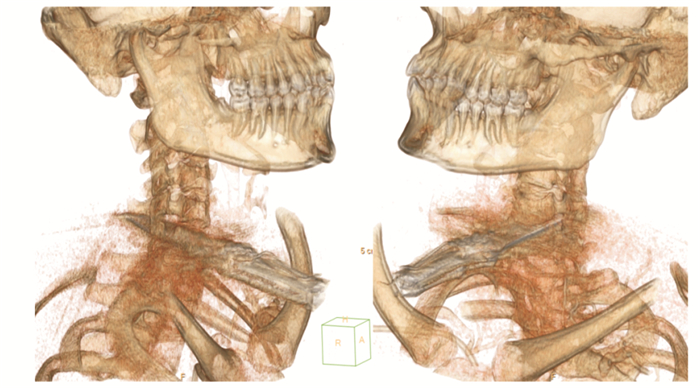

| 图 4 头颈胸部CT重建 |

|

|